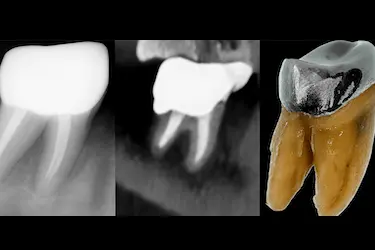

TAC para endodoncia

Especialmente en los casos complejos donde necesitamos imágenes detalladas de los conductos radiculares y estructuras internas del diente.

Ayuda a localizar conductos accesorios y lesiones periapicales que no se aprecian en radiografías convencionales.